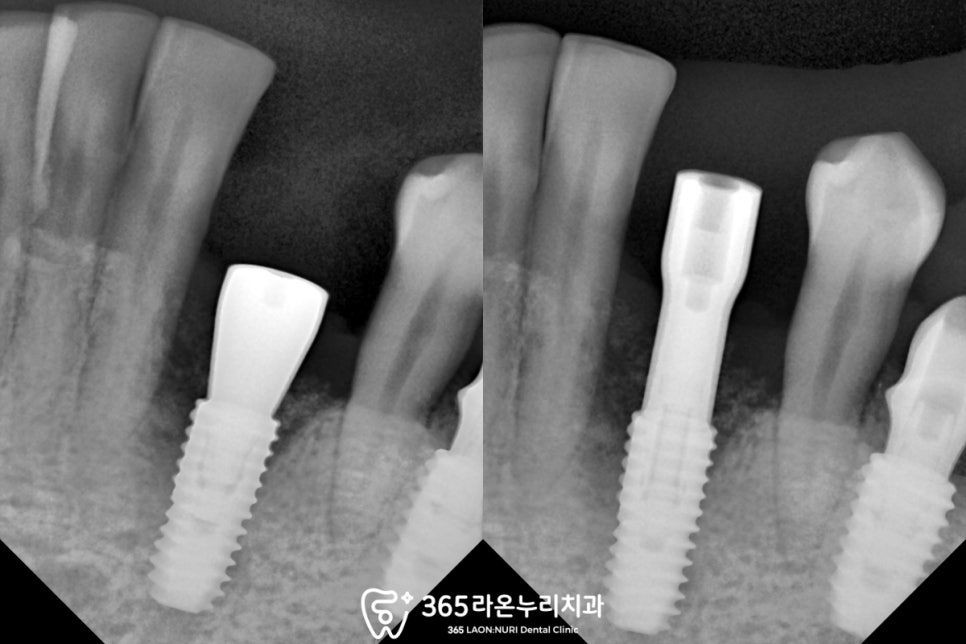

파노라마는 구강 전체가 나오는 사진이라

치근단 사진을 찍어 한 번 더 살펴보았습니다.

보이는 것처럼 뿌리를 잡아주는

주변의 잇몸뼈가 녹아

까맣게 보이죠?

이렇게 되면 우리우리한 통증과 함께

이가 흔들리게 됩니다.

다시 본론으로 돌아와

픽스처와 뼈가 잘 결합되었다면

어버트먼트를 연결합니다.

그리고 이 위로

임시치아를 올려드리게 되는데